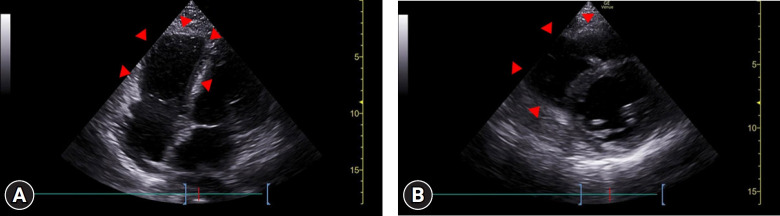

Aortic dissection in pregnant patients results in an inpatient mortality rate of 8.6%. Owing to the pronounced mortality rate and speed at which aortic dissections progress, efficient early detection methods are crucial. Here, we highlight the importance of early chest computed tomography (CT) for differentiating aortic dissection from pulmonary embolism in pregnant patients with dyspnea. We present the unique case of a 38-year-old pregnant woman with elevated D-dimer and N-terminal pro-brain natriuretic peptide (NT-proBNP) levels, initially suspected of having a pulmonary embolism. Initial transthoracic echocardiography did not indicate aortic dissection. Surprisingly, after an emergency cesarean section, a chest CT scan revealed a DeBakey type I aortic dissection, indicating a diagnostic error. Our findings emphasize the need for early chest CT in pregnant patients with dyspnea and elevated D-dimer and NT-proBNP levels. This case report highlights the critical importance of considering both aortic dissection and pulmonary embolism in the differential diagnosis of such cases, which will inform future clinical practice.

Abstract Image